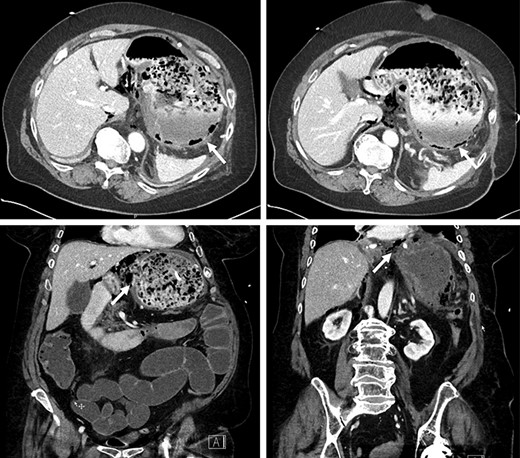

The patient mentioned after surgery that her symptoms started after ingesting a significant quantity of maize. In the postoperative period, the patient developed a fungemia to Candida glabrata that was treated accordingly. No intra-abdominal complications occurred. A barium swallow was performed in the postoperative period to assess the integrity of the esophagojejunal and jejunojejunal anastomoses. No leak was objectified (Fig. 2). The patient was successfully discharged home after a hospital stay of 20 days. The feeding jejunostomy tube was removed 2 months later. No outpatient complications were noted except mild deconditioning that required physical therapy.

Intact esophagojejunal and jejunojejunal anastomoses on barium swallow.